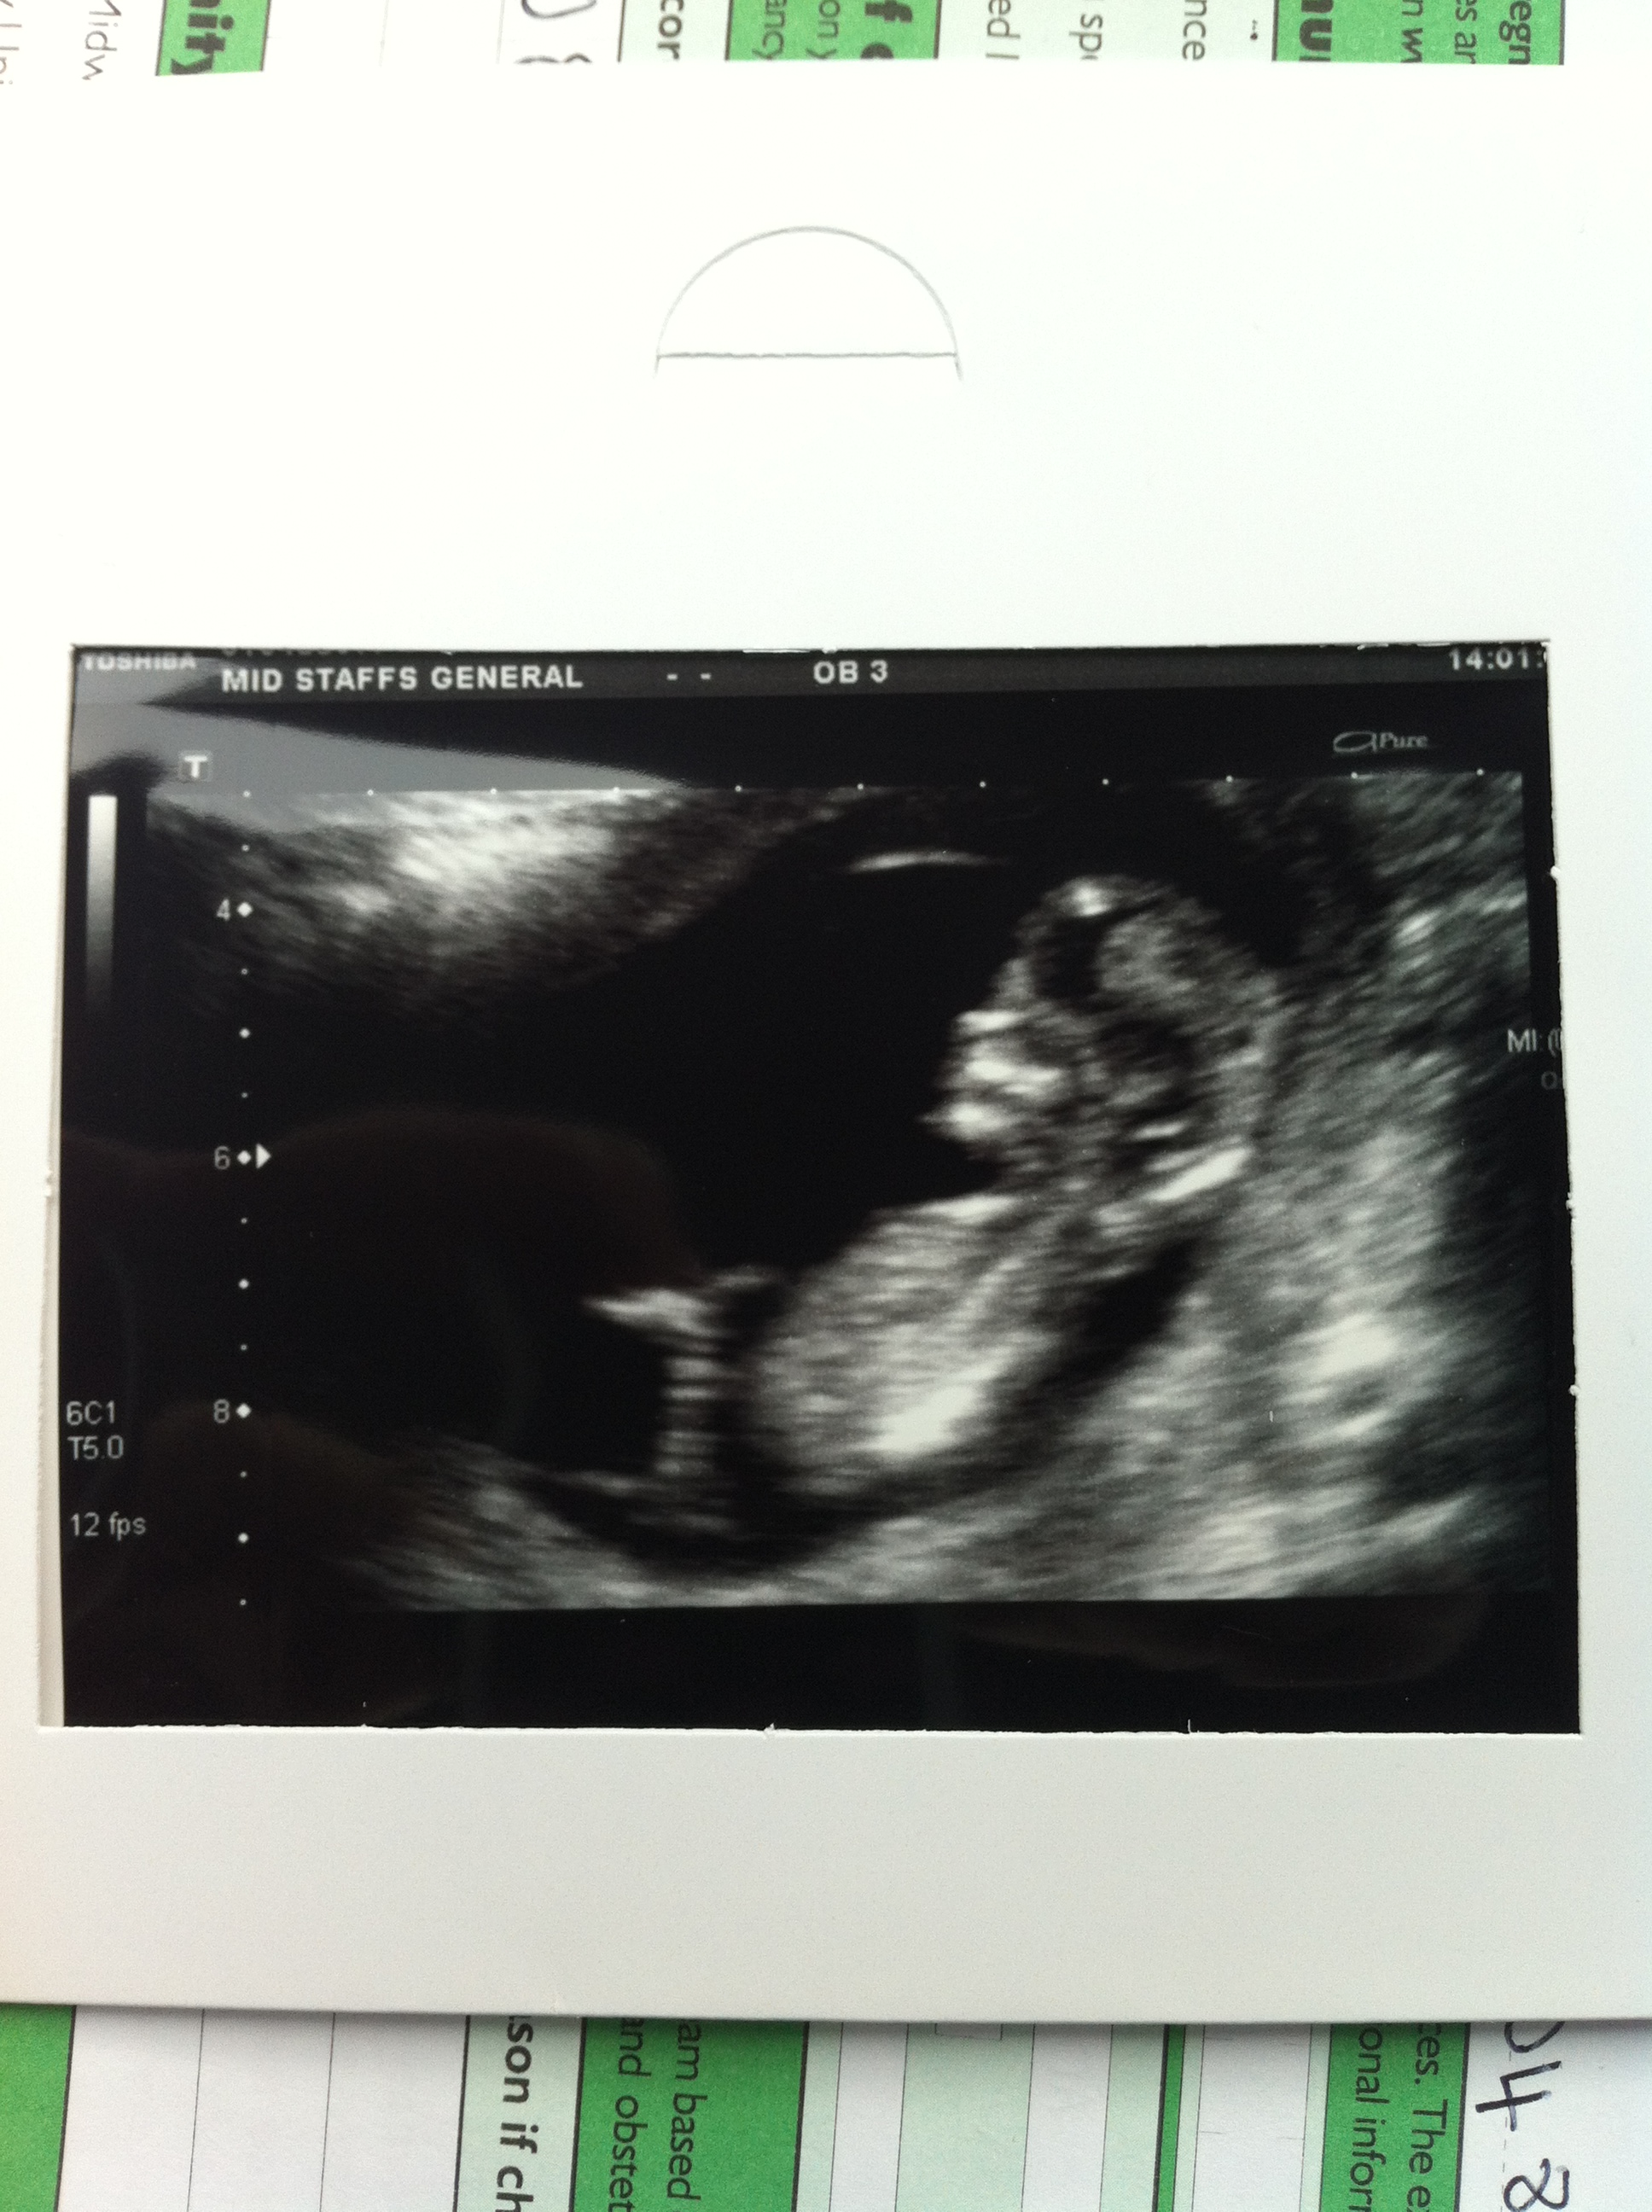

Here is my 12 week scan pictures, I was dated at 13 weeks 2 days any thoughts on boy or girl either nub or skull theory will be very much appreciated.

Skull looks boyish to me, but I'm not sure about the nub. What are you hoping for? Either way, good luck!! :)

Guessing boy from skull but it could be a nub in pic 2 which looks to be pointing up xx

I don't really see a nub so hard to tell